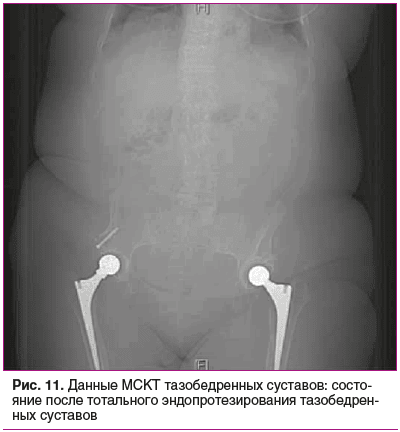

Мультиспиральная компьютерная томография (МСКТ) тазобедренных суставов (рис. 11): состояние после тотального эндопротезирования тазобедренных суставов.